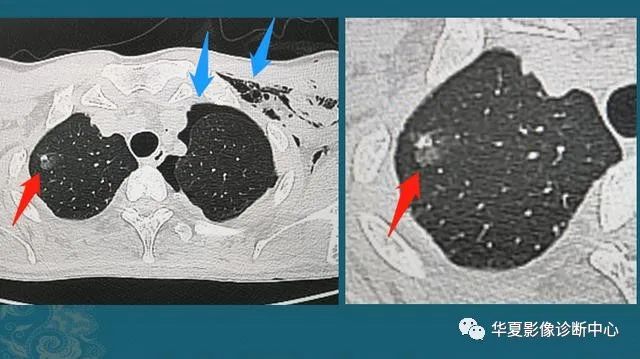

下图是一位30岁年轻人,车祸外伤,撞断3根肋骨,并造成肺挫伤、出血(创伤性湿肺):

红箭头这里的一小片肺组织被车祸撞击暴力撕裂,小血管破裂出血,形成不均匀的高密度影;蓝箭头是气胸和皮下气肿(肺破了,肺里空气溢出到胸腔和肌肉间隙内)。

这种程度的创伤没有生命危险,保守治疗1周出院了,后来小伙子复查CT,肺里留下了一个3 mm的光滑小结节:

这是个良性实性小结节,是血肿吸收不彻底形成的,不要紧,不需要定期复查。